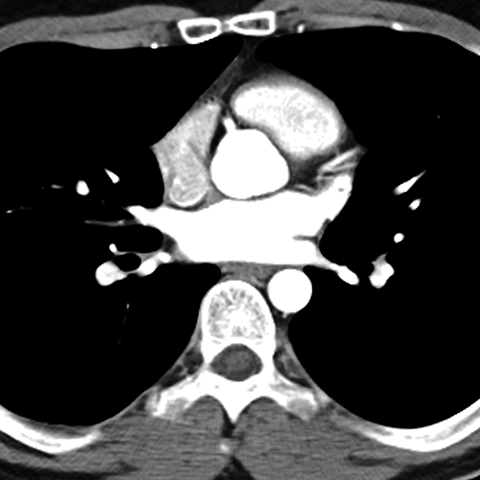

Normal Heart (CT) [5 of 6]